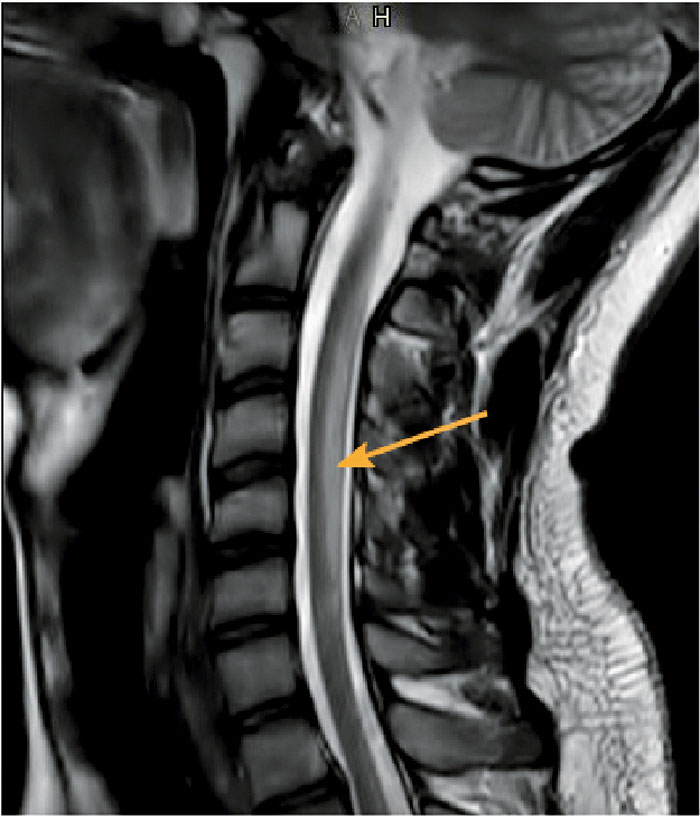

Vid återbesök hos neurolog efter 3 veckor var patienten avsevärt förbättrad och hade knappt några sen­soriska bortfall, men fortsatt något nedsatt balans. En uppföljande MR-undersökning 2 veckor därpå visade kvarstående signalförändringar i ryggmärgen, utan kontrastuppladdning (Figur 2). Patienten remitterades till primärvården 5 månader senare och hade då endast kvar en diskret domning lateralt i ena lilltån.

Figur 2. MR halsrygg 5 veckor efter insjuknande. Sagittal T2-viktad bild. Patienten var i detta skede kliniskt klart förbättrad, men uppvisade fortfarande tydligt patologisk MR-bild (pil). På en T1-viktad bild med kontrast (ej visad) såg man dock att kontrastuppladdningen gått i regress.